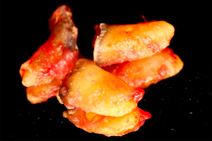

- Non-surgical periodontal therapy was performed to reduce gingival inflammation and swelling

- Surgical removal of excessive gum tissues and extraction of multiple poor prognosis teeth were carried out as well